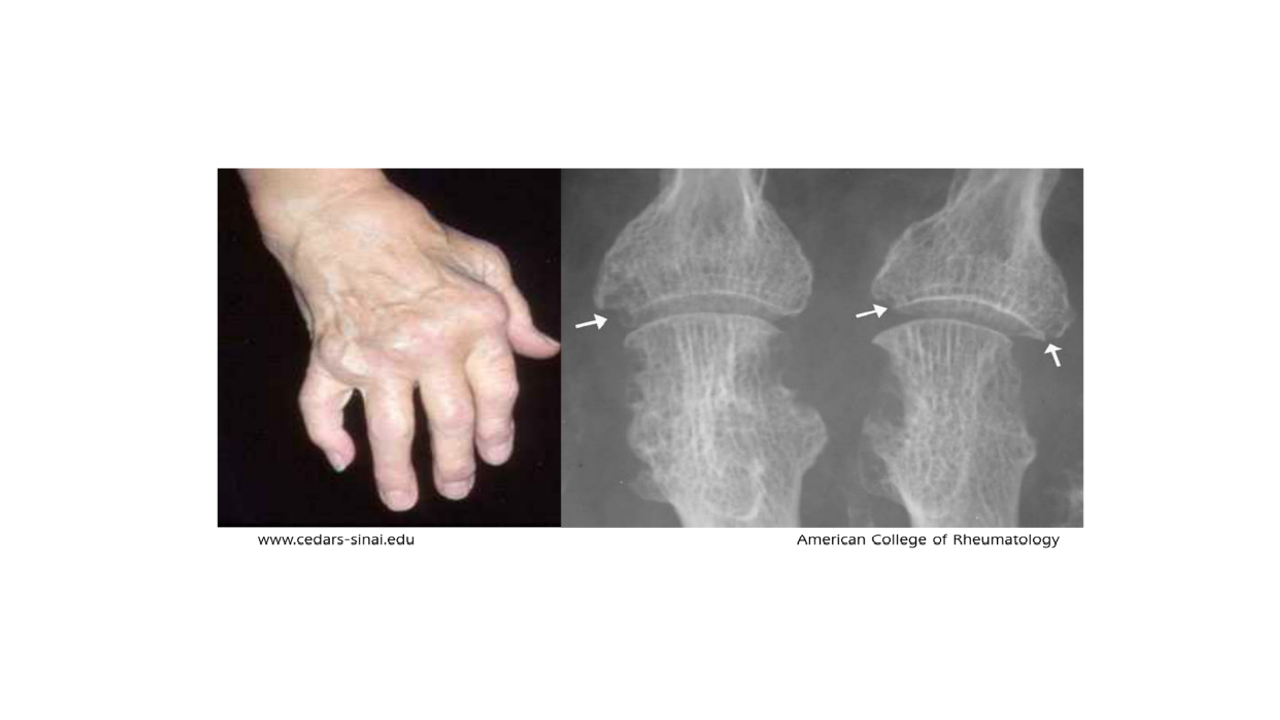

자가 항체에 의한 반복적인 관절염증으로 인해 관절 파괴와 변형이 일어나는 질환입니다.

손이나 발의 작은 관절에서 시작해 어깨, 무릎 등 다양한 관절 부위에 통증이 발생합니다.

진단